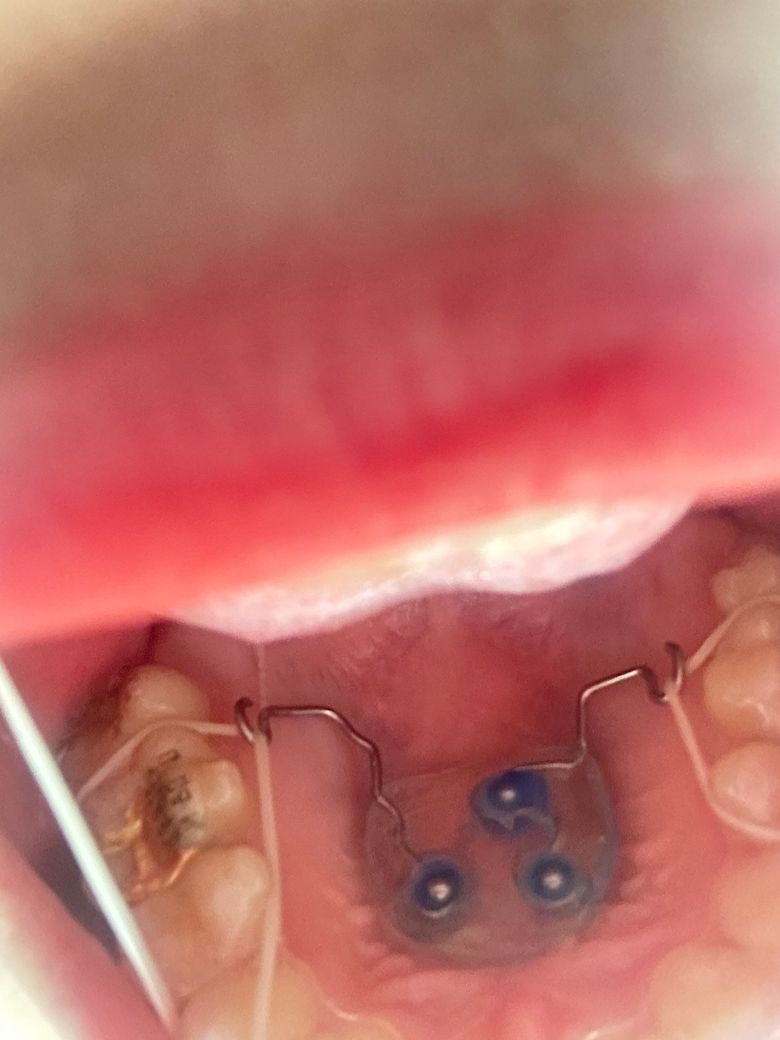

교정 때문에 입천장에 확장장치를 부착했는데

저 판이랑 입천장 사이가 진짜 좁고 음식물이 잘 빠질만한 공간이 아니라 음식물이 다 끼는데 빠지진 않아요…. 진짜 뭐 먹을 때마다 물치실을 20분씩 해서 입천장 다 까질 것 같아요 혹시 꿀팁 있을까요 칫솔질 못합니다 그정도 틈이 아니에요…

• 1번 째 사진